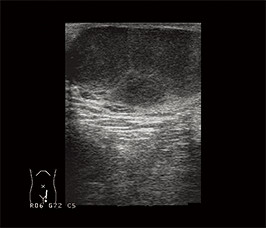

停留精巣

鼠径管内を検索する。これは小児の症例であるが、成人でもしばしば精巣は萎縮しており、停留している精巣は小さくしか描出されない。

精巣